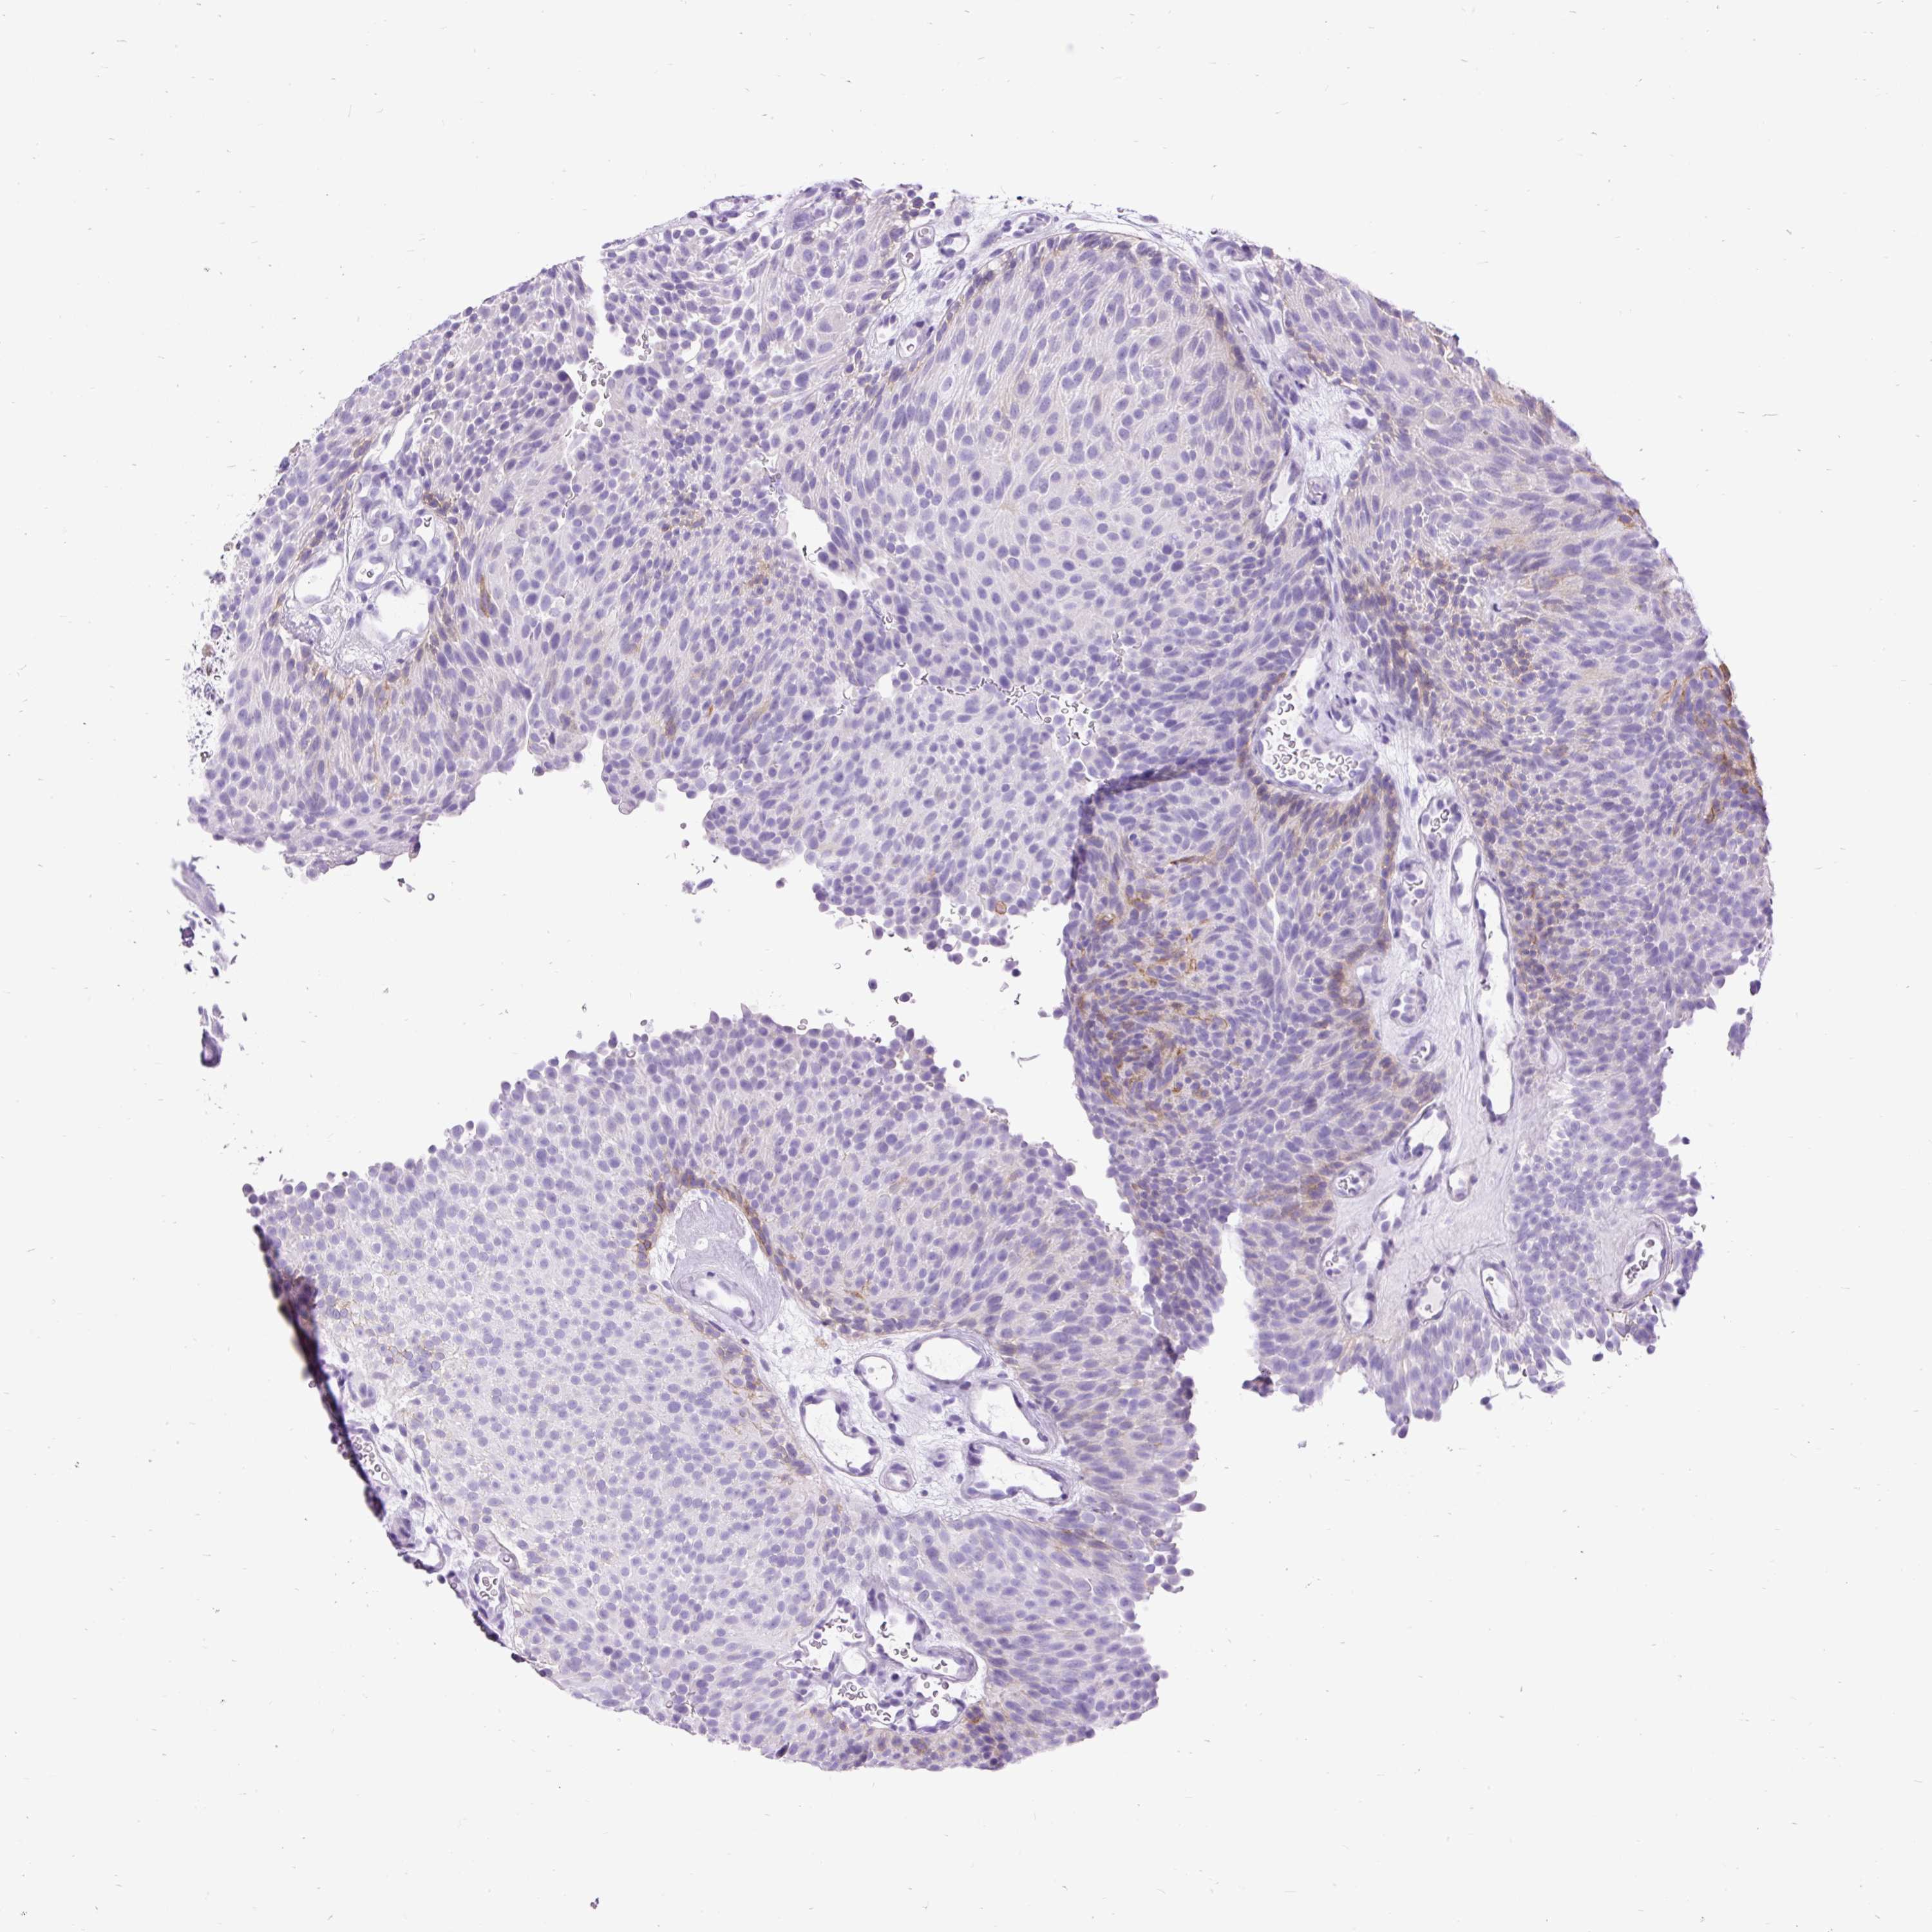

UROTHELIAL CANCER - Protein expressioni

A mouse-over function shows sample information and annotation data. Click on an image to view it in a full screen mode. Samples can be filtered based on level of antibody staining by selecting one or several of the following categories: high, medium, low and not detected. The assay and annotation is described here.

Note that samples used for immunohistochemistry by the Human Protein Atlas do not correspond to samples in the TCGA dataset.

Antibody stainingi

Antibody staining in the annotated cell types in the current human tissue is reported as not detected, low, medium, or high, based on conventional immunohistochemistry profiling in selected tissues. This score is based on the combination of the staining intensity and fraction of stained cells.

Each image is clickable and will lead to virtual microscopy that enables deeper exploration of all samples and also displays staining intensity scores, fraction scores and subcellular localization as well as patient and tissue information for each sample.

Antibody HPA051692

Antibody HPA053492

Urothelial carcinoma, High grade

Urothelial carcinoma, Low grade

Urothelial carcinoma, NOS